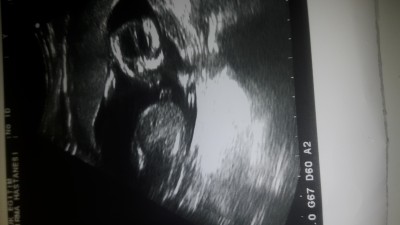

14+5 gunluk hamileyim tecrubeli anneler cinsiyet tahmini yaparmisimiz

Gebelik haftası 14+5